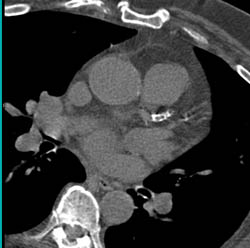

Extensive Coronary Artery Calcification